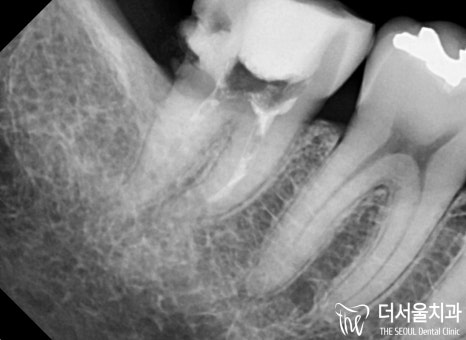

『드디어 모든 과정이 끝났습니다.』

구치부라 잘 안 보이니깐

그냥 만들어도 되겠지~

생각할 수 있는데요.

위아래가 제대로 맞물리지 않고

옆에 치아와 거리가 떨어져 있는 등

심각한 문제로도 이어질 수 있죠.

더서울에서는 이 모든 사항을

고려하여 제작하였기 때문에

최선의 결과를 안겨드릴 수 있었습니다^__^